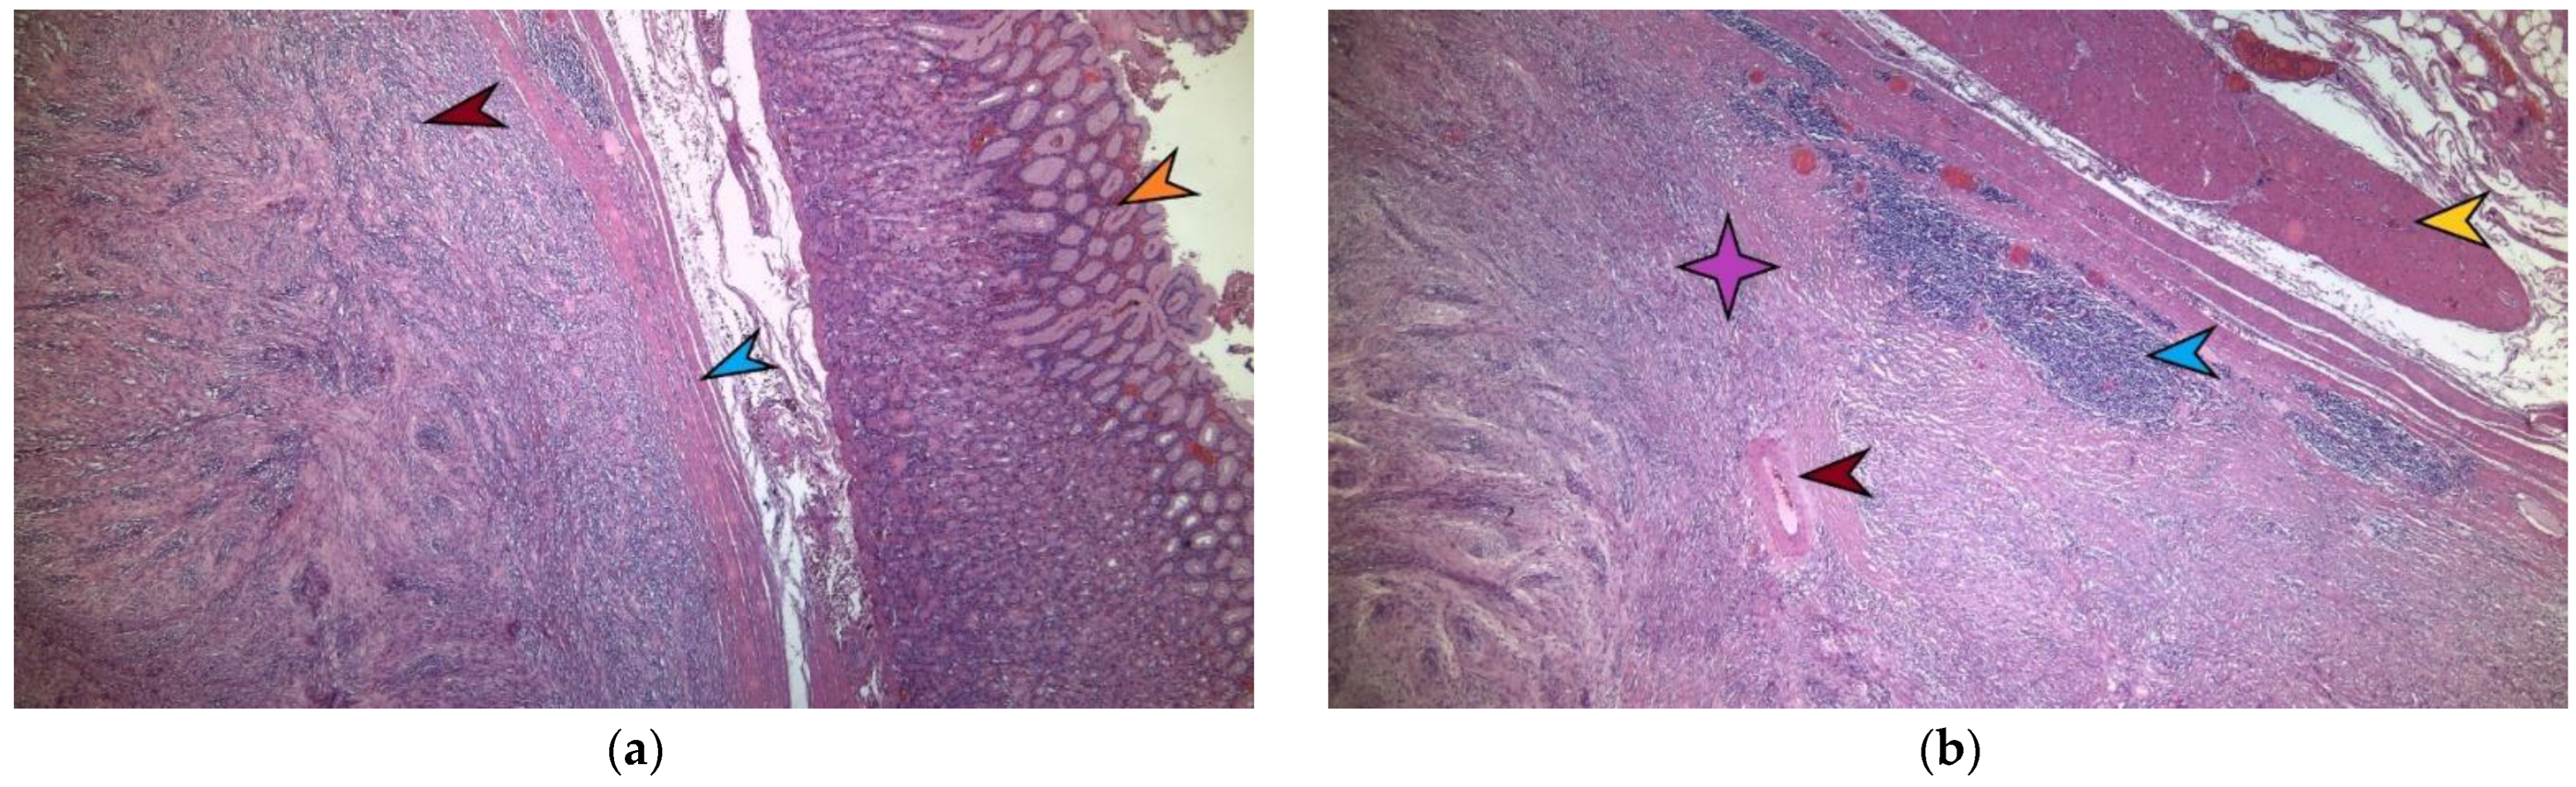

A microscopic image of tumor formation in hematoxylin–eosin stain, ×4 magnification. The red arrow marks the tumor formation originating from the stomach’s own muscular layer. The blue arrow indicates the stomach’s own muscular layer, and the yellow arrow indicates the normal-looking gastric mucosa above it (a). A detailed microscopic image of a gastric schwannoma in hematoxylin–eosin stain, ×10. The purple star indicates the tumoral mass made of monomorphic fusiform cells with eosinophilic cytoplasm and elongated nuclei, where no mitotic activity and no intratumoral necrosis are identified. The red arrow indicates an intratumoral blood vessel with hyalinized walls. At the periphery of the tumor, lymphoid-cuffing aggregates are evident, marked by the blue arrow. The yellow arrow marks the muscularis propria of the stomach (b). Microscopically, in hematoxylin–eosin staining, a well-delimited nodular tumor proliferation is detected and develops at the level of the gastric muscle proper. This tumor consist of monomorphic fusiform cells with an eosinophilic cytoplasm and elongated nuclei, with no mitotic activity identified, and with no intratumoral necrosis (Figure 5a,b). Thus, the exact type of tumor is determined by the immunohistochemical determination of CD117, CD 34, SMA—smooth muscle actin, and desmin—which are negative in this case. CD 117 is a marker that is present in gastrointestinal stromal tumors (GIST) and is expressed by the c-kit tyrosine kinase receptor and Cajal cells in the intestine [7].